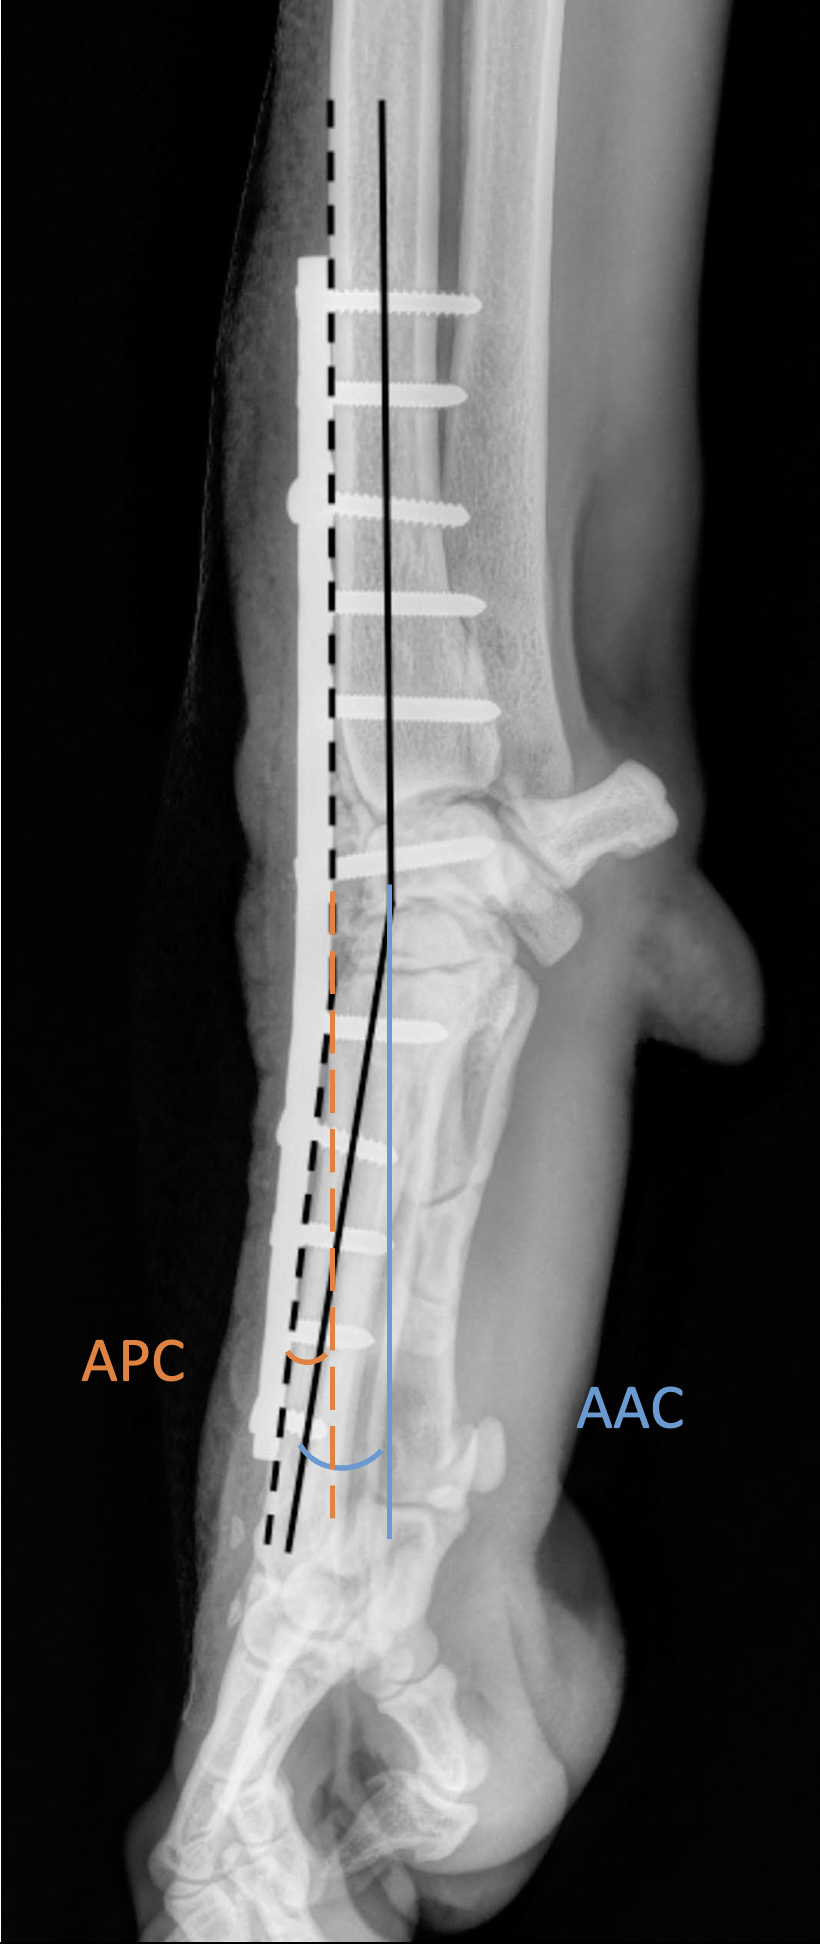

Le placement dorsal ou latéral, le type de plaque, l'utilisation d'un champ chirurgical adhésif ou le type de greffe n'étaient pas associés au taux de retrait. Cependant, l'angle de la plaque d'APC et l'angle d'arthrodèse carpienne (voir l'illustration principale) ont significativement influencé ce taux, qui était plus élevé chez les chiens présentant un degré d'hyperextension plus faible. L'angle médian de la plaque d'APC pour les cas d'explantation était de 3,6° (±4,2°) et de 6,6° (±3,1°) pour les cas de non-explantation. De plus, la valeur médiane de l'angle d'arthrodèse carpienne était de 11,73° (± 3,78°) pour les cas de non-explantation et de 8,58° (±4,86°) pour les cas d'explantation, montrant une association significative avec le statut d'explantation. Les auteurs précisent que la règle générale veut que l'angle d'hyperextension post-APC se rapproche de l'angle physiologique de 10 à 15 degrés. Mais il n'y a pas beaucoup de marge, car une diminution de l'extension physiologique du carpe peut causer un stress excessif sur les articulations métacarpo-phalangiennes, tandis qu'un plus grand degré d'extension augmente le levier des forces par rapport à la plaque.